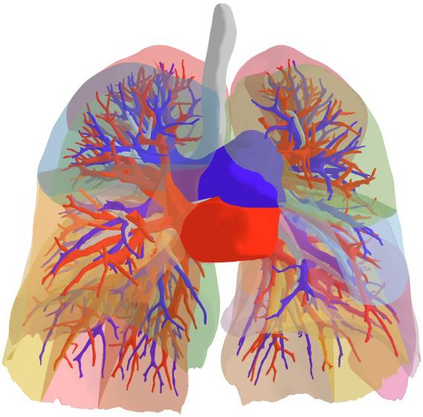

3D reconstruction of pulmonary segments plays an important role in surgical treatment planning of lung cancer, which facilitates preservation of pulmonary function and helps ensure low recurrence rates. However, automatic reconstruction of pulmonary segments remains unexplored in the era of deep learning. In this paper, we investigate what makes for automatic reconstruction of pulmonary segments. First and foremost, we formulate, clinically and geometrically, the anatomical definitions of pulmonary segments, and propose evaluation metrics adhering to these definitions. Second, we propose ImPulSe (Implicit Pulmonary Segment), a deep implicit surface model designed for pulmonary segment reconstruction. The automatic reconstruction of pulmonary segments by ImPulSe is accurate in metrics and visually appealing. Compared with canonical segmentation methods, ImPulSe outputs continuous predictions of arbitrary resolutions with higher training efficiency and fewer parameters. Lastly, we experiment with different network inputs to analyze what matters in the task of pulmonary segment reconstruction. Our code is available at https://github.com/M3DV/ImPulSe.